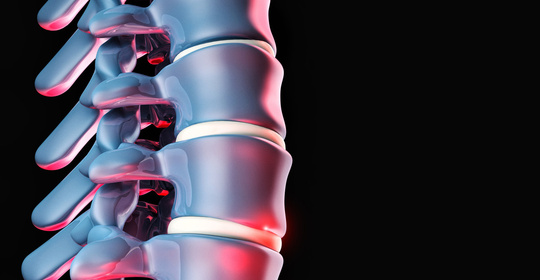

脊神經壓迫:背部的煎熬,症狀與科學疏導方法詳解